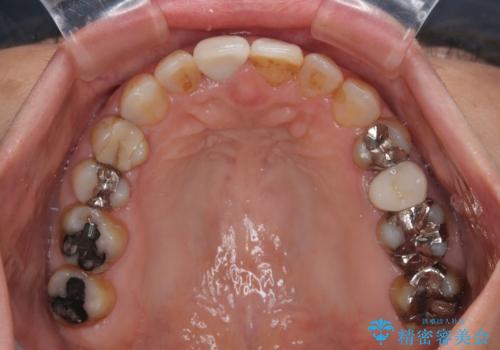

- 上下前歯のデコボコと、治療途中の歯を気にして来院された患者様です。

根管治療が必要な歯は事前に処置を行った上で矯正治療を開始し、概ね歯列が整ったところでセラミッククラウンなどに置き換え、その後インビザラインを1セット使用して仕上げていくこととしました。